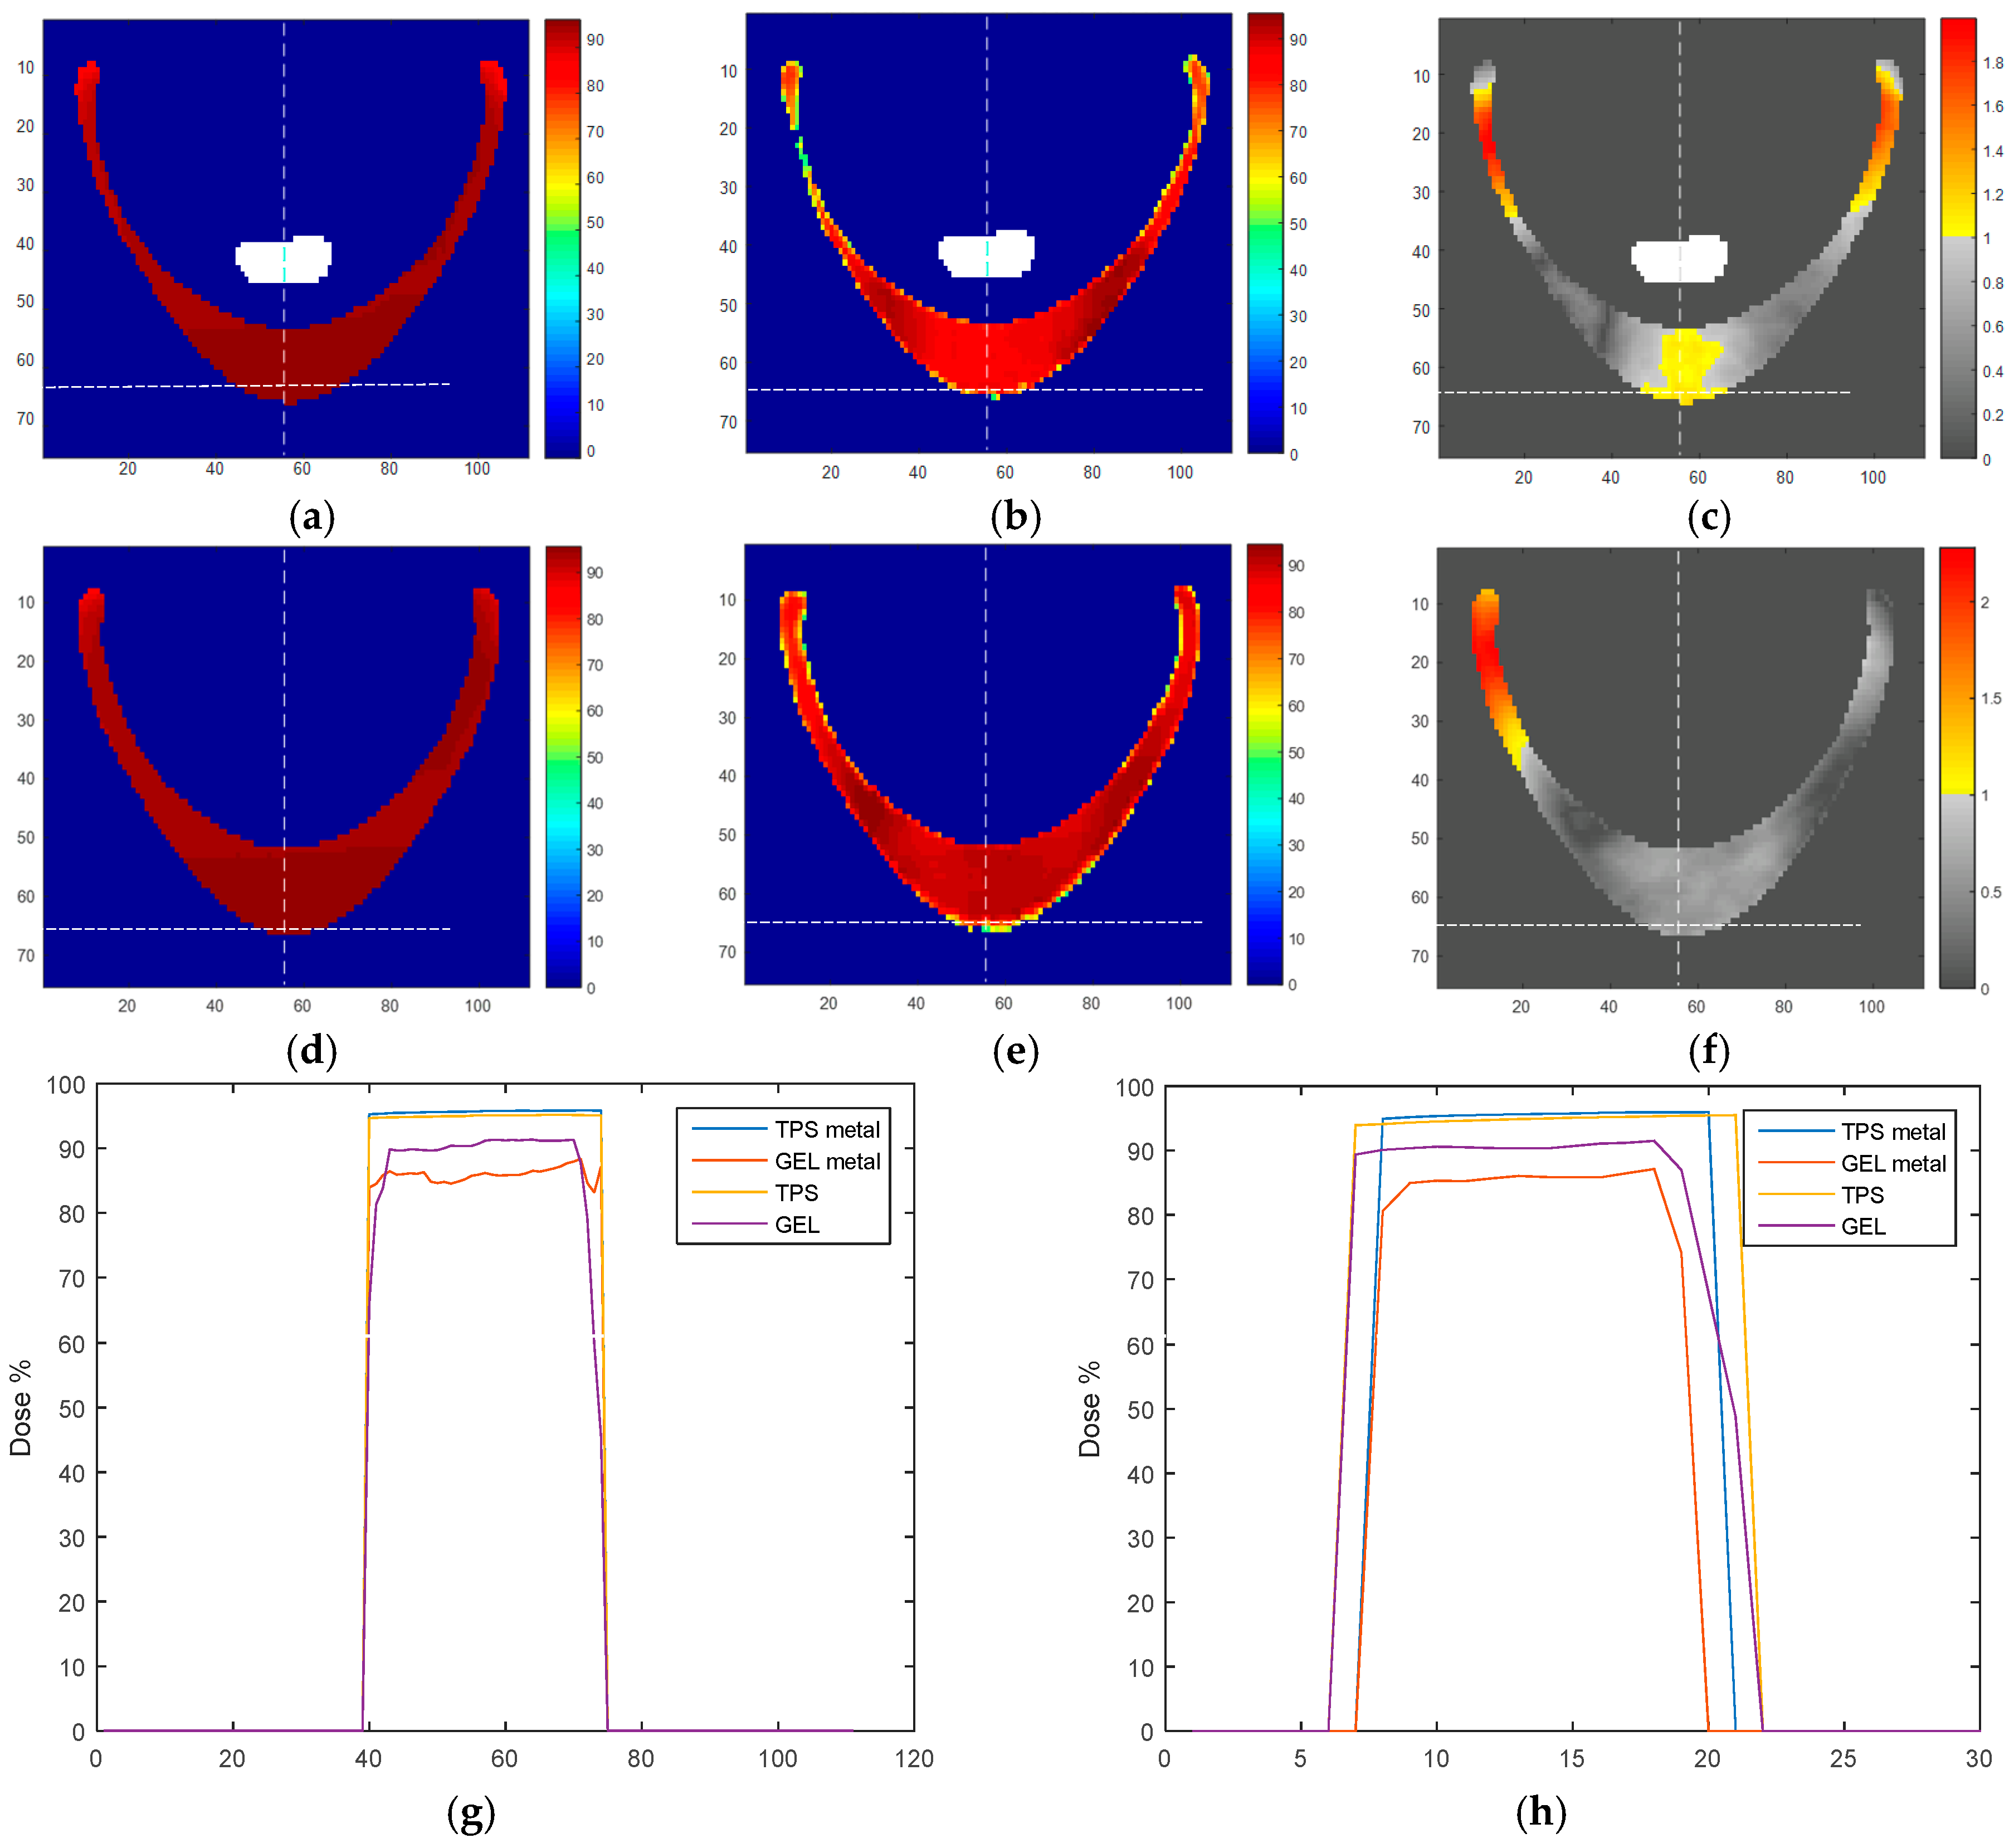

2. Results and Discussion

4. Materials and Methods